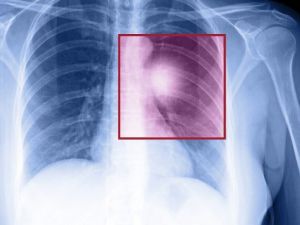

Doç. Dr. Kılıçkap: “Son 5 Yılda Akciğer Kanserine Yönelik Daha Etkili Tedaviler Geliştirildi”